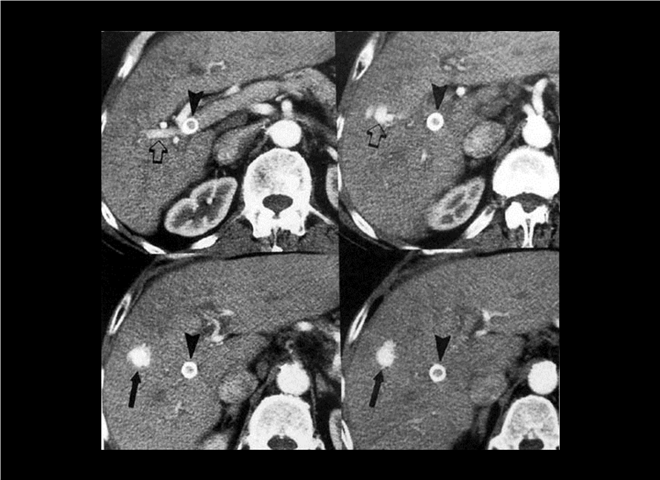

13_CT增强扫描